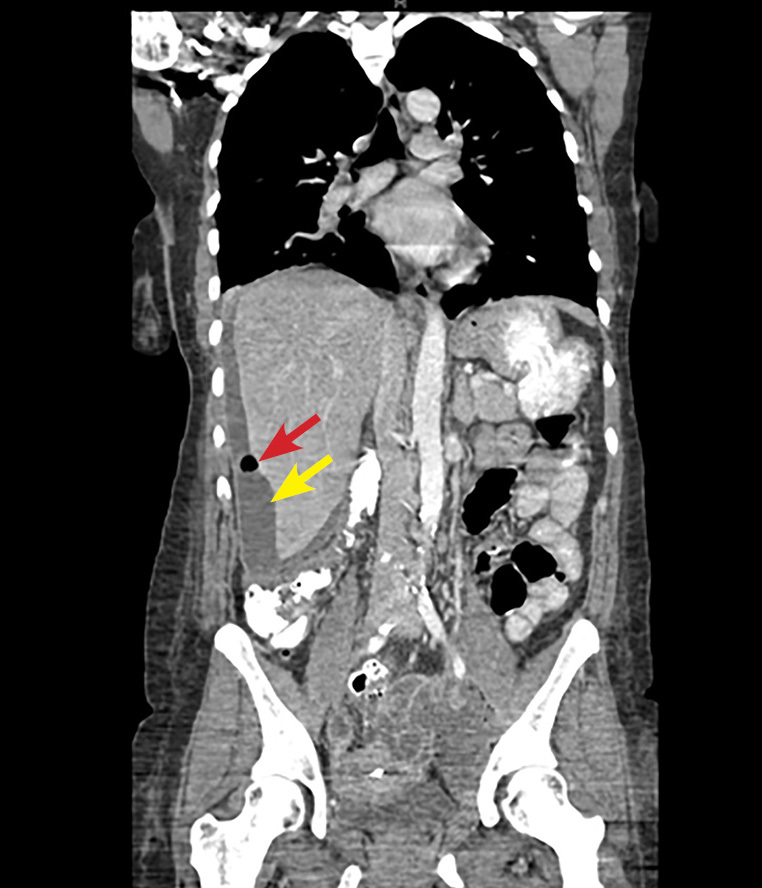

A definitive diagnosis is made laparoscopically by visualizing adhesions resembling violin strings or by hepatic capsular biopsy to identify causative organisms. Noninvasive diagnostic modalities, such as ultrasound, may show fluid collections and widening of the subphrenic area between the liver and the diaphragm. On CT scan, hepatic capsular enhancement may be seen. (See Figure 3.)

Figure 3. Coronal CT Scan Shows an IUD in the Mid Pelvis with a Left Adnexal Abscess and a Perihepatic Subcapsular Abscess with Air |

Perihepatic subcapsular abscess indicated by white arrow. Air indicated by black arrow. CT: computed tomography; IUD: intrauterine device Image courtesy of Basil Hubbi, MD, Department of Radiology, Rutgers New Jersey Medical School. |